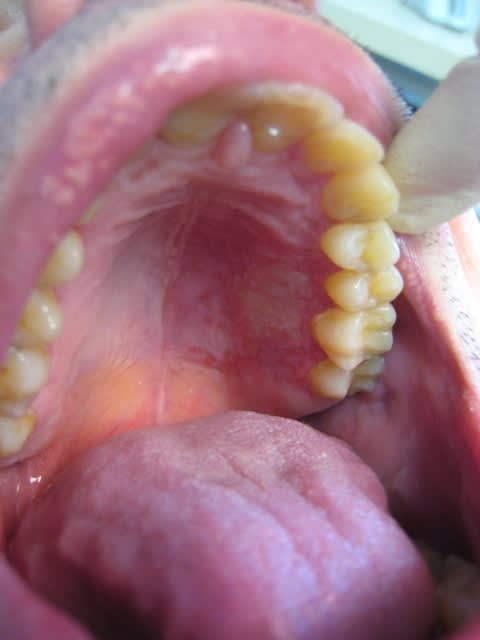

J'ai reçu un patient en urgence samedi dernier pour une lésion palatine en regard de 25,26. Il y a ulcération blanche d'un bon centimètre de diamètre entourée de petits points rouges. Les dents sont vitales, légèrements mobiles mais cela est plus lié à un contexte paro à mon avis.

Il me dit qu'environ 4 jours auparavant, il a décollé une sorte de "peau" au niveau du palais en se brossant les dents. Il pense qu'il y avait quelque chose déjà avant.

La lésion est douloureuse au contact, aux aliments acides. Il a des douleurs qui le lance jusque dans l'oeil et l'oreille.

Est-il possible que ce soit une lésion de zona ? Il me semble que l'hémi-palais gauche est oedématié avec une limite nette au niveau du raphé.